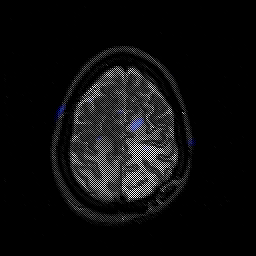

Glioblastoma multiforme overlay -- Slice #42

[Home][Help][Clinical][Tour 1][Tour 2][Tour 3] Slice 42